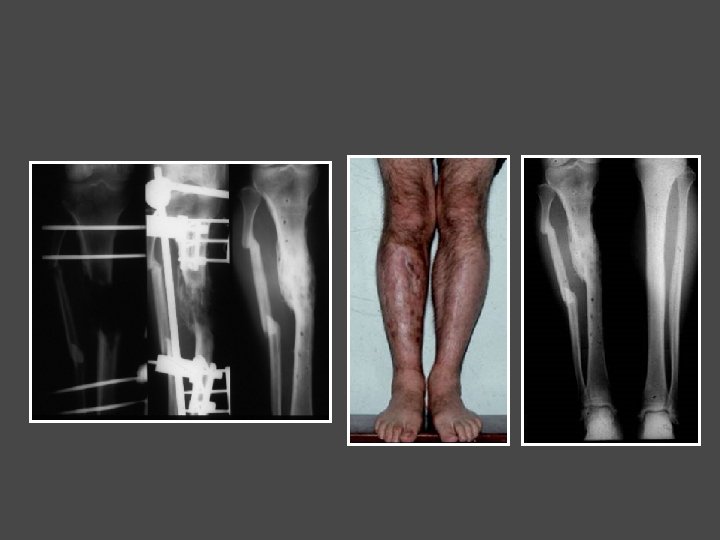

Papineau sur pseudarthrose infectée du tibia

Papineau sur pseudarthrose infectée du tibia Curetage + fixateur Greffe osseuse + correction de l’équinisme